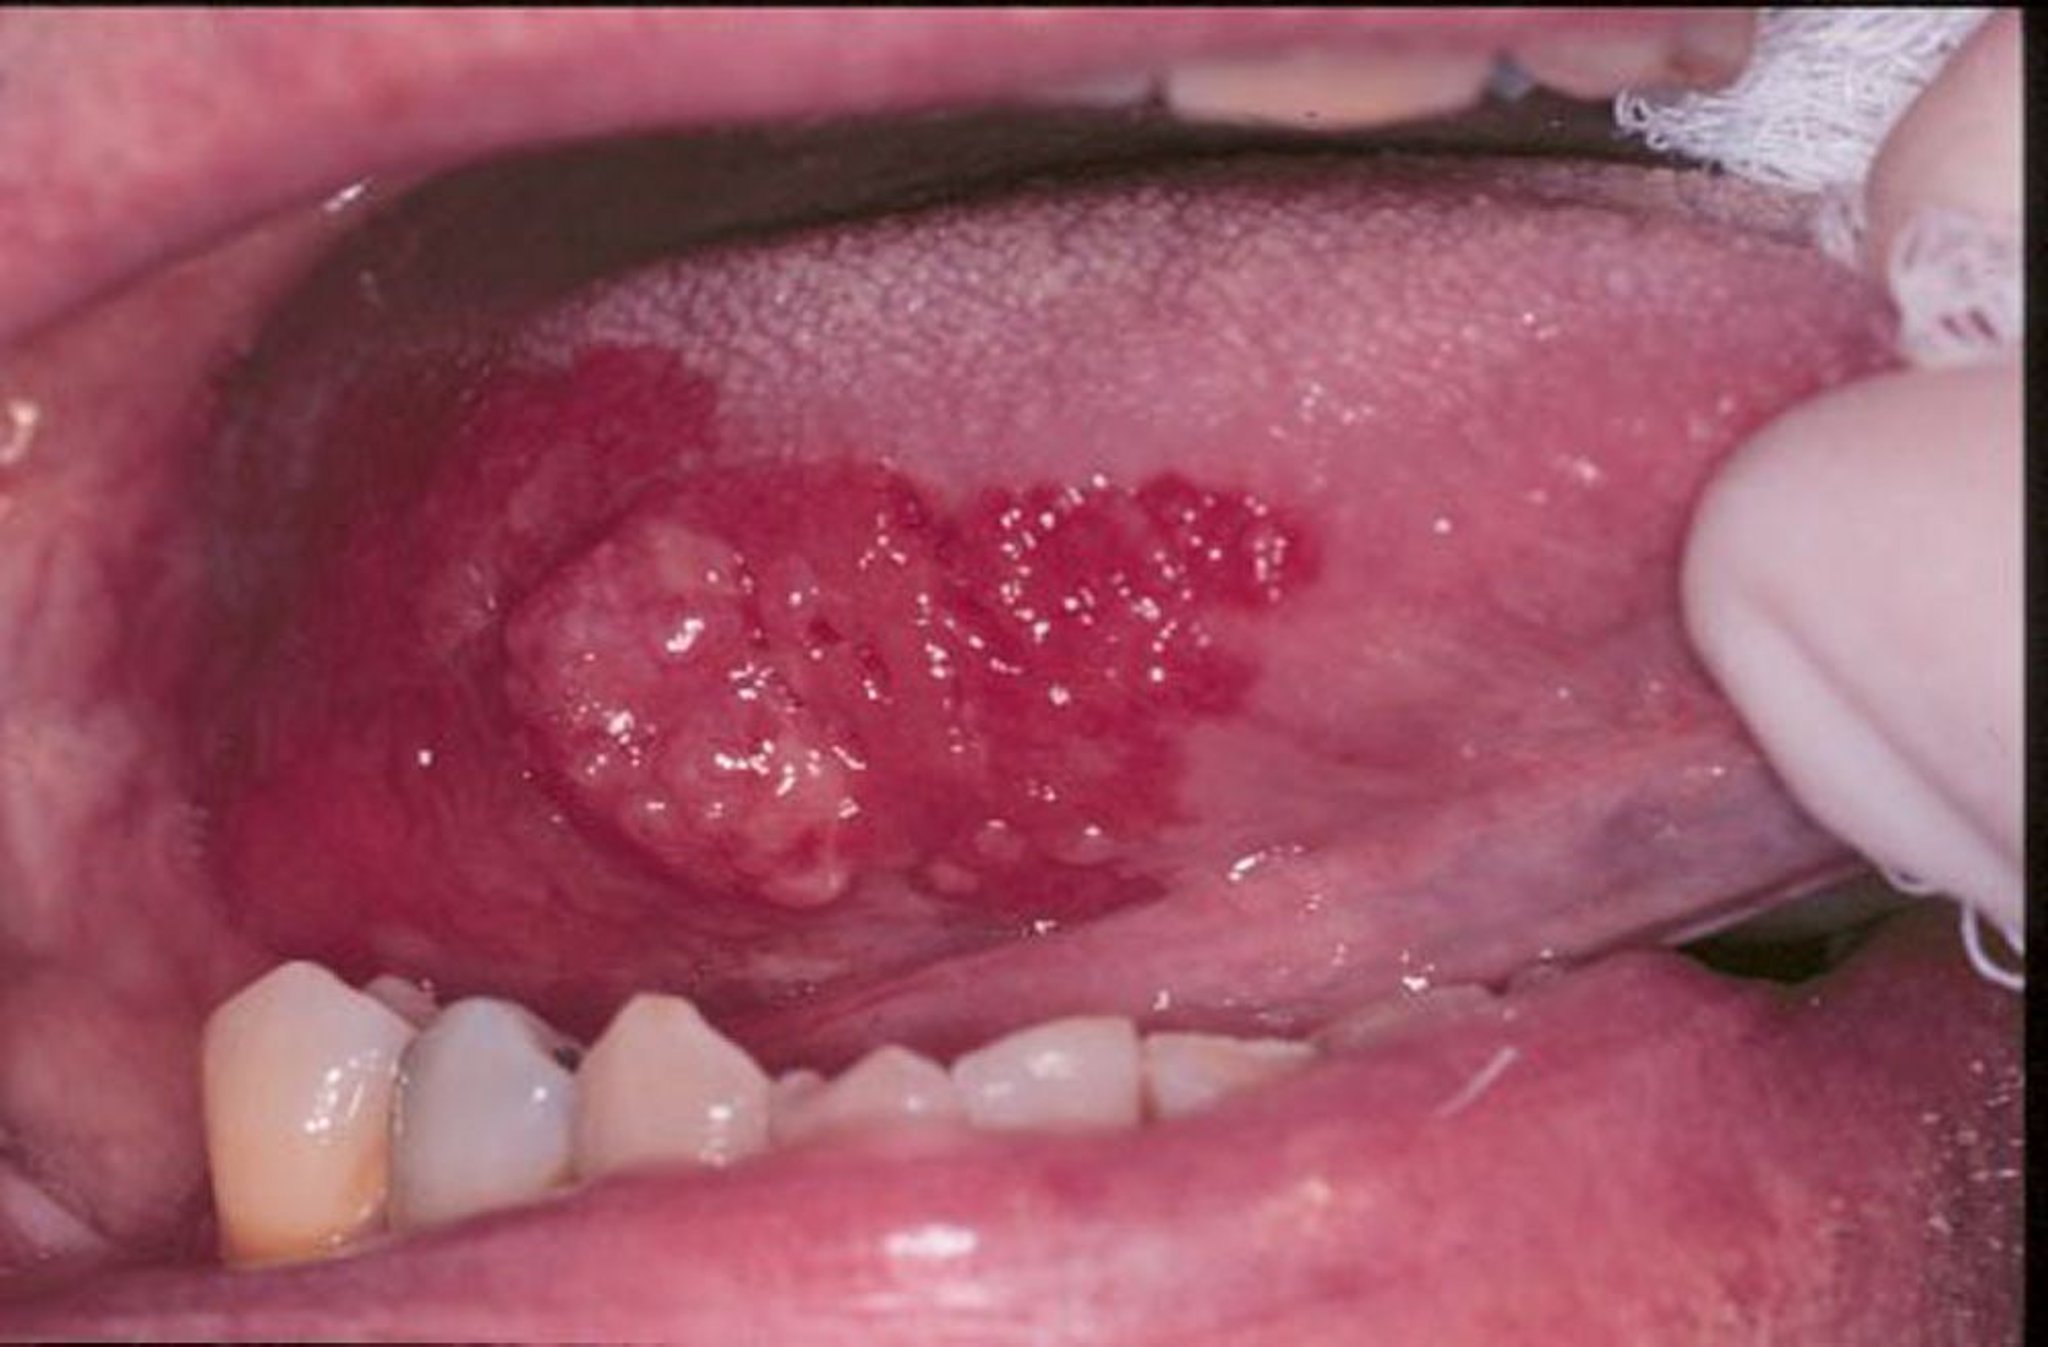

एरिथ्रोप्लेकिया और स्क्वेमस सेल कार्सिनोमा

एरिथ्रोप्लेकिया मुंह में विकसित होने वाले लाल, सपाट, या घिसे-पिटे मखमली दिखने वाले घावों के लिए एक सामान्य शब्द है। इस इमेज में, स्क्वेमस सेल कार्सिनोमा के आसपास एरिथ्रोप्लेकिया फैल जाता है।

इमेज जोनाथन ए. शिप, DMD द्वारा प्रदान की गई है।